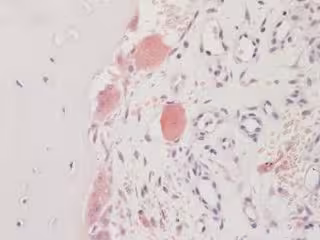

Archivo - Osteoporosis

Archivo - Osteoporosis - SHEFFIELD UNIVERSITY - Archivo